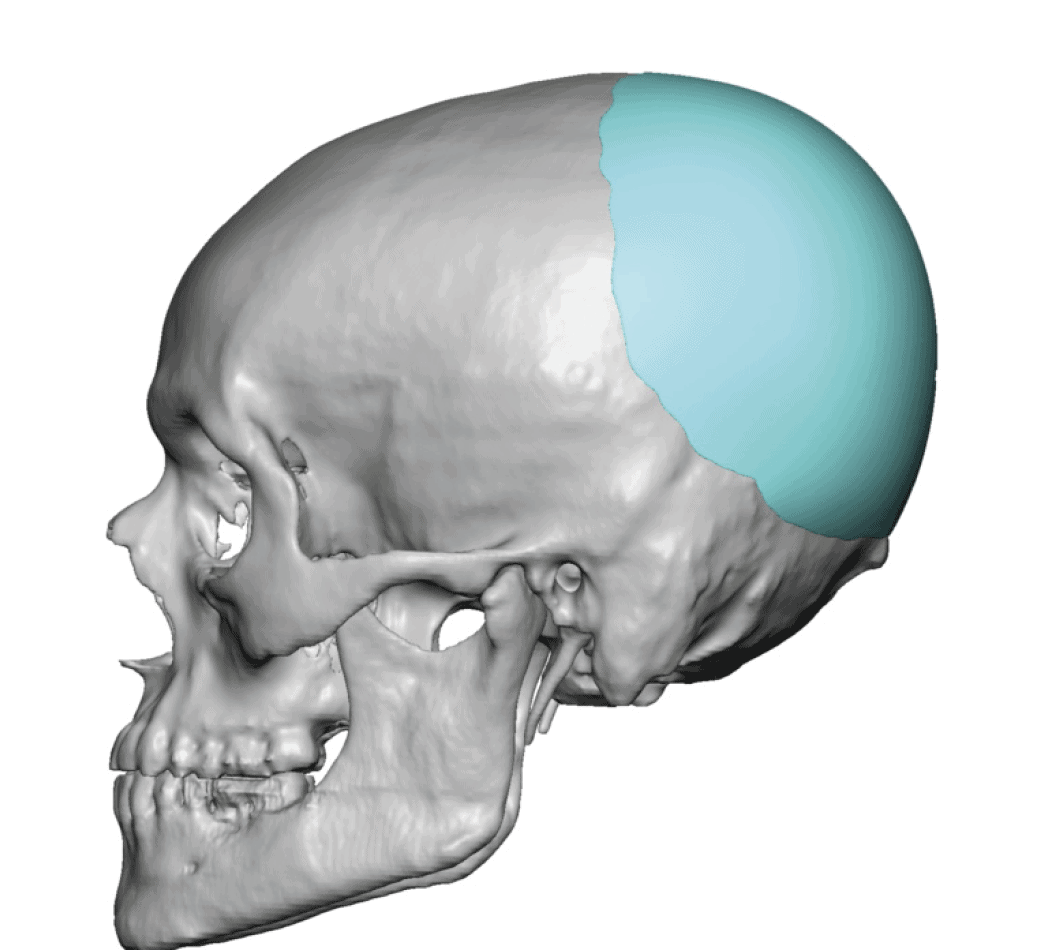

Patient 51

Desire for taller and rounder head shape.

Two stage custom skull implant augmentation technique.